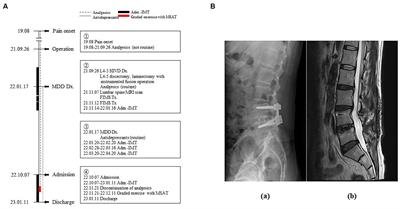

In his medical history, the patient had been diagnosed with L4–5 HIVD and had undergone discectomy and laminectomy with instrumented fusion in September 2021. Before diagnosis and surgery, he received no treatment other than arbitrary analgesic administration when the pain was severe. Although the surgery was successful with no abnormal findings on magnetic resonance imaging (MRI) or computed tomography (CT), the patient had no symptomatic changes in the lower back or lower extremities (Figure 1B). Subsequently, he had to be discharged from the army because of disturbance in his activities of daily living, which had become strikingly worse than before becoming diseased. Moreover, following two ineffective functional intramuscular stimulation (FIMS) treatments, the patient developed helplessness and hopelessness. This triggered depression, manifesting as sleep disturbance, reduced appetite, pessimism regarding his symptoms, and a subsequent attempted suicide. Later that year, he was diagnosed with MDD. Four admissions for integrative medicine treatment, before and after the diagnosis of MDD, did not indicate any pain management strategies (Figure 1A).

Figure 1. Timeline of the patient’s medical history. (A) Timeline of the medical events between the onset of the pain and the current treatment period. Narrative demonstrations of the timeline are in the boxes. (B) Radiological images of the lumbar spine (a: lateral view of X-ray image, b: Sagittal section of T2-weighted magnetic resonance image). Adm, admission; Dx, diagnosis; FIMS, functional intramuscular stimulation; HIVD, herniated intervertebral disc; IMT, integrative medicine treatment; MDD, major depressive disorder; MRI, magnetic resonance imaging; MSAT, motions style acupuncture therapy; Tx, treatment.